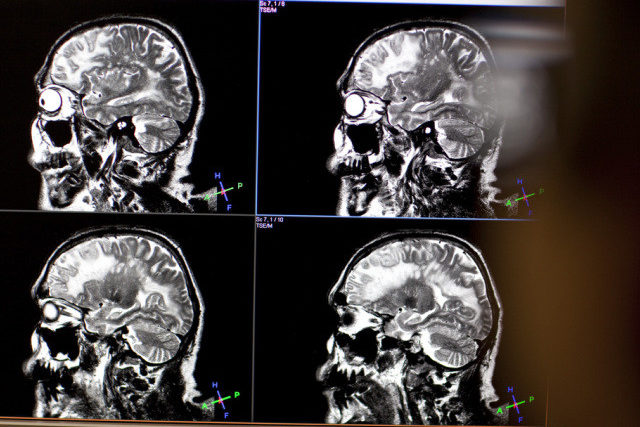

Hirnaktivität-Messung im Kernspintomograph an Uni Zürich (Archiv) (Bild: sda)